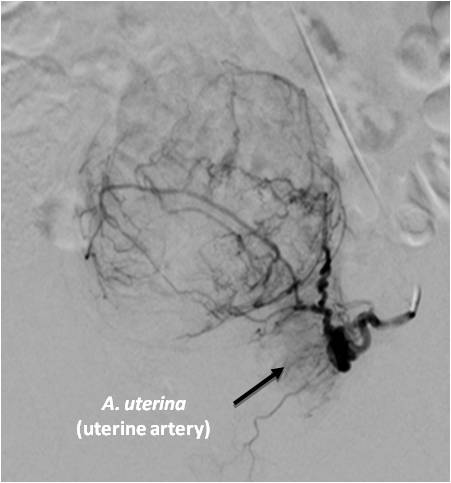

In the endovascular intervention in UL, special attention is paid to the segment of the uterine artery that ascends towards the uterine-tubal angle and gives off numerous tortuous branches directly to the uterine body and cervix (the zone of direct branching of the uterine artery into the terminal branches) (Figure 2).

Fig. 2. A selective angiogram of the left uterine artery of a female patient Z., 40 years, after embolization with preservation of the isthmic and vaginal branches.

The uterine artery is usually a tortuous artery that is well visualized throughout its entire length (both the trunk and its small branches) (Figure 3).

Fig. 3. A selective angiogram of the left uterine artery after embolization of the uterine arteries: uterine-ovarian anastomosis.

The degree of blood supply to the nodules depends on their arrangement in the myometrium. In the presence of large subserous nodules, the branches of the uterine artery in the area of formation lose their characteristic tortuosity, are expanded and strained, and are located around the myomatous nodule. The inner part of the formation is poorly vascularized, the accumulation of contrast agent in the parenchymal phase is sharply weakened. With the intramural and submucous nodules, there is a more pronounced perifibroid accumulation of vessels in the layer on the periphery of the structure and intense contrast of the parenchyma in this zone (Figures 4, 5).

The tubal part of the uterine artery often actively anastomoses with ovarian vessels. Wide anasto-moses in this area can become the cause of restoration of blood supply to myomatous nodules (Figure 6).